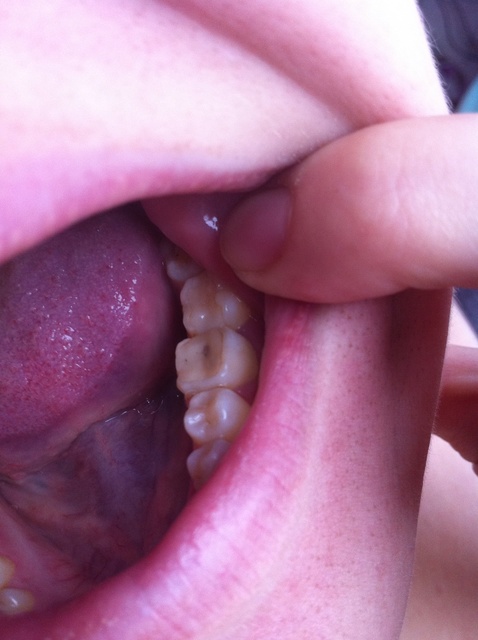

Данный зуб необходимо лечить,т.к. вокруг пломбы кариес и пломба как бы отслаивается. Такие зубы часто скалываются, а пломбы продолжают стоять(

Черные стрелки указывают на отслойку пломбы, желтая- на кариес под плобой ( такая серость под эмалью)